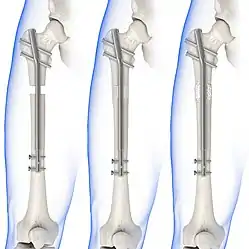

Distraction osteogenesis

Open-reduction surgery is typically not performed at the level of the proximal fibula, as dissection near the proximal end may risk severing the common peroneal nerve. Instead, reducing the proximal fibula at the level of the distal tibiofibular syndesmosis is recommended.[6][12] A hook test is performed, using a curved hook, to assess the stability of the fibula. If instability is detected, further distraction of the fibula can be done to repair the full bone. The fibula can then be guided into the fibular notch located on the tibia, effectively restoring its length. Internal rotation of the foot may then be used to correct anatomical alignment.[12][13]

Following open-reduction, internal fixation is usually performed to stabilise the ankle mortise. To account for the distal fibula being slightly posterior to the distal tibia, drill holes are angled at 30° from the anteromedial aspect of the tibia to the posterolateral aspect of the fibula.[4][12][15] Trans-syndesmotic screws can be inserted in this way to ensure tibia fixation. Additional supra-syndesmotic screws may be temporarily inserted, for approximately 3 to 6 months, if instability is still present after fibular reduction. To reduce the fibula and restore the ankle mortise to its proper anatomical configuration, partial dorsiflexion of the foot is maintained prior to intraoperative screw fixation. This is because, in a neutral or maximally dorsiflexed position of the foot, the trochlear surface of the talus may reduce maximal postoperative dorsiflexion due to rigidity after screw fixation.[9][12]